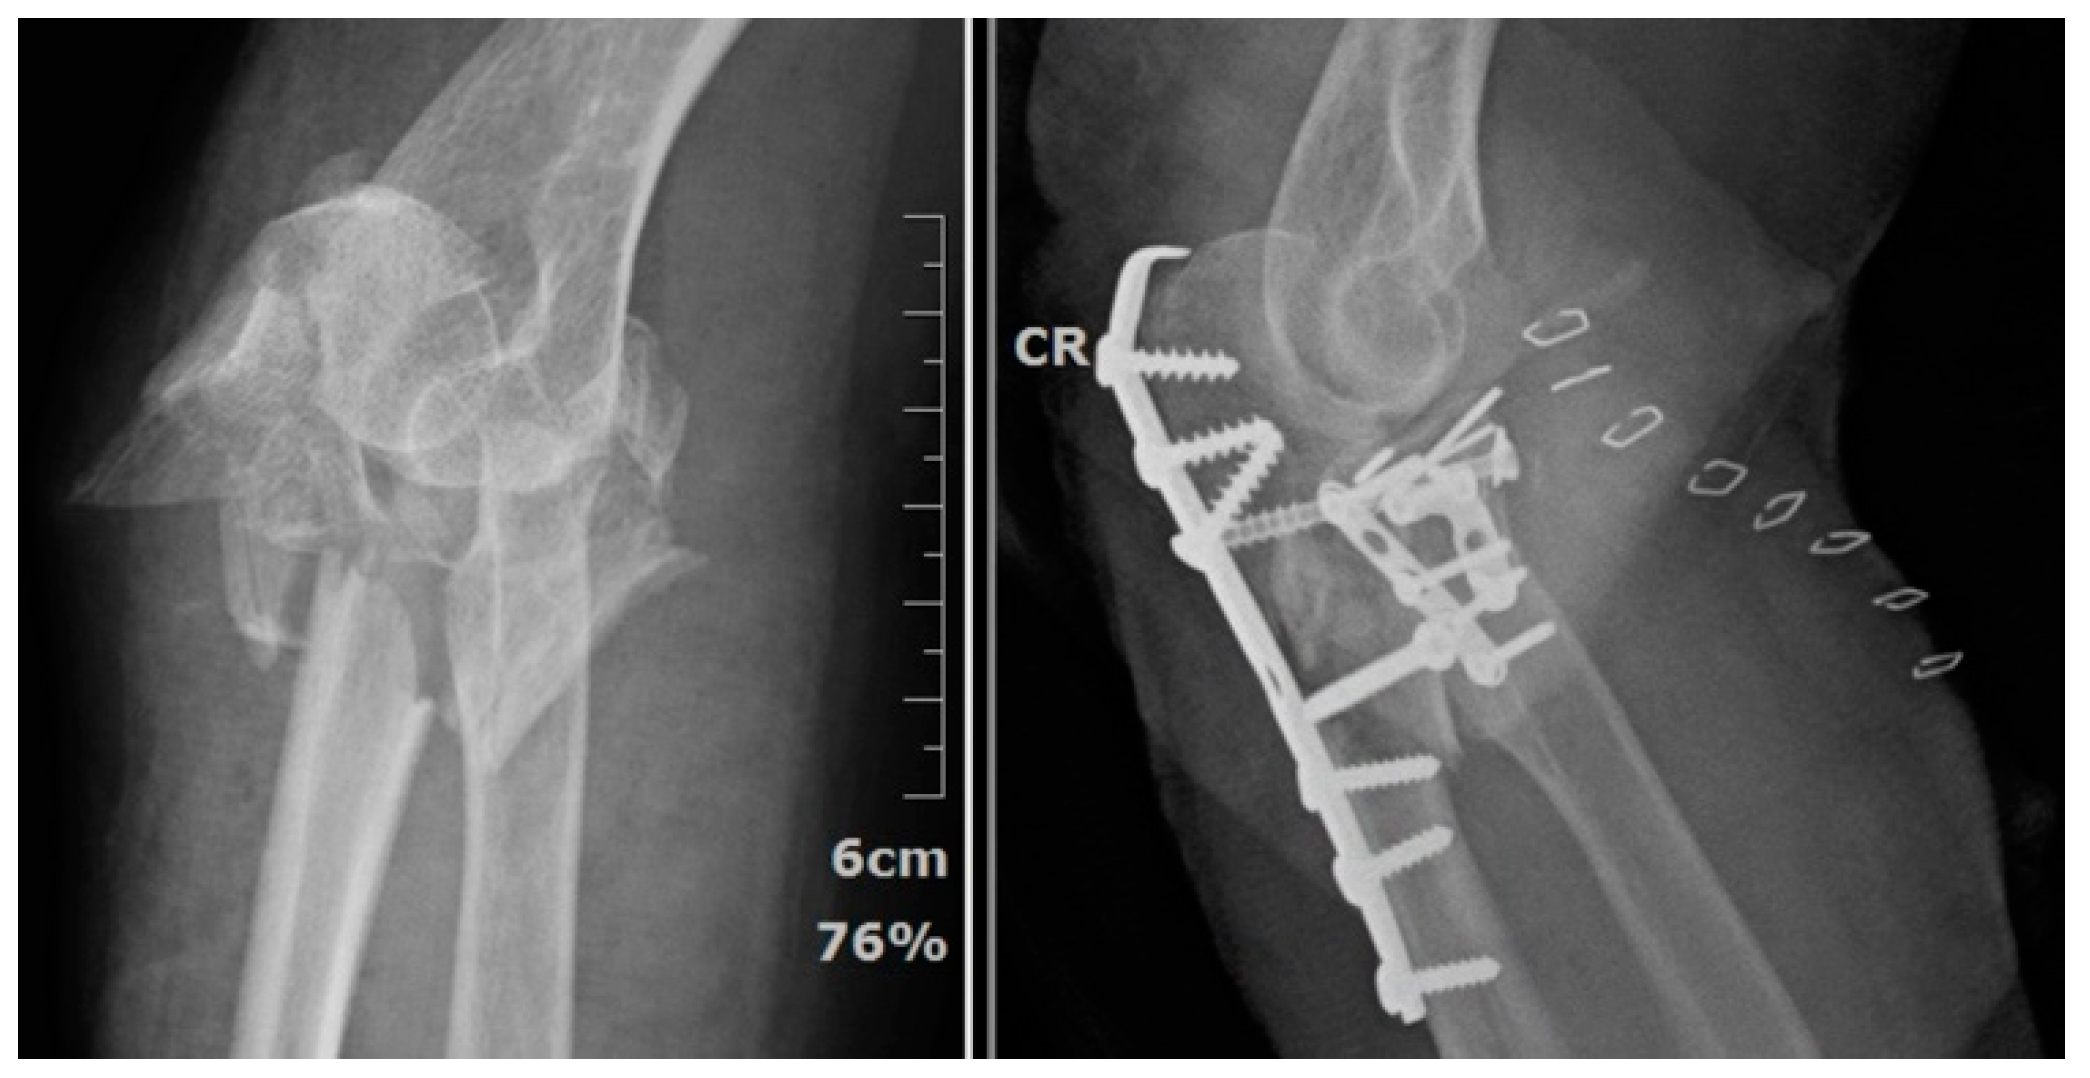

2.2. Steps of Fixing Coronoid Process Anteriorly

2.3. Fixation of Radial Head

2.4. Variant Proximal Ulnar Fractures and Ligaments Injuries